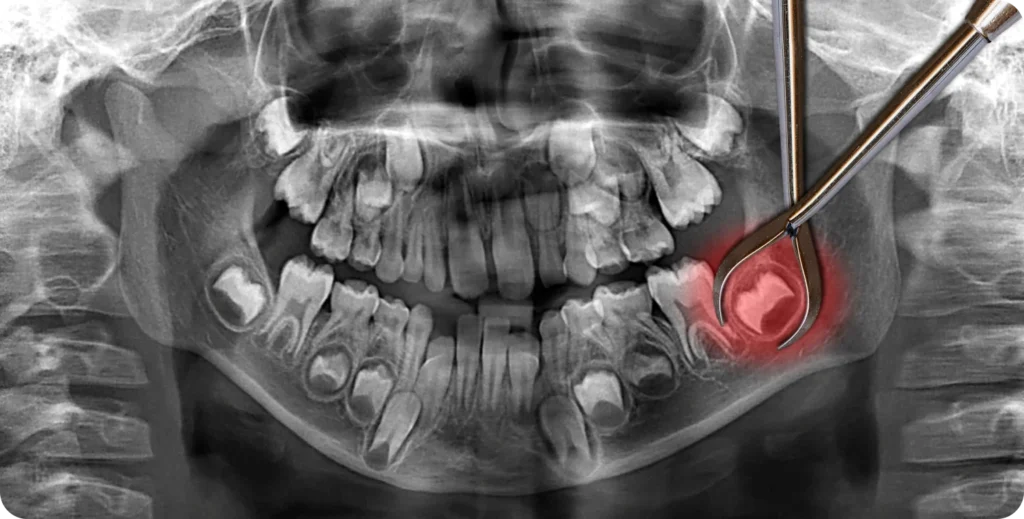

Une dent incluse est une dent qui reste partiellement ou complètement enfouie dans la gencive. Cela peut affecter les dents de sagesse, les canines, ou même d’autres dents. Les dents incluses peuvent causer des douleurs, des infections, et des problèmes d’alignement dentaire. Pour résoudre ce problème, un traitement orthodontique spécifique est souvent nécessaire.

Dans certains cas, les dents incluses peuvent être associées à la formation de kystes ou de tumeurs. Les kystes dentaires sont des sacs remplis de liquide qui se forment autour des dents non éruptées. Ces kystes peuvent se développer et causer des dommages aux os de la mâchoire et aux dents adjacentes. Les tumeurs, bien que rares, peuvent également se développer autour des dents incluses, nécessitant une intervention chirurgicale complexe.

La première étape du traitement consiste en une évaluation complète. L’orthodontiste utilise des radiographies pour localiser la dent incluse. Ensuite, il évalue la situation et planifie le traitement approprié. Cette évaluation est cruciale pour déterminer la meilleure approche.

La chirurgie de dégagement est souvent nécessaire pour les dents profondément incluses. Pendant cette procédure, le chirurgien expose la dent incluse en enlevant une partie de la gencive et de l’os qui la recouvrent. Cette intervention facilite l’accès à la dent pour l’orthodontiste.

L’intervention commence par l’administration d’une anesthésie locale pour engourdir la zone. Dans certains cas, une sédation consciente ou une anesthésie générale peut être utilisée, surtout si la dent est profondément enfouie ou si le patient est anxieux. Une incision est ensuite pratiquée dans la gencive pour exposer la dent incluse.

Une fois la gencive incisée, le chirurgien utilise des instruments spécialisés pour retirer une petite quantité d’os recouvrant la dent. Cette étape est délicate et nécessite une grande précision pour éviter d’endommager les structures adjacentes. La dent est alors exposée, permettant au chirurgien de l’accéder directement.